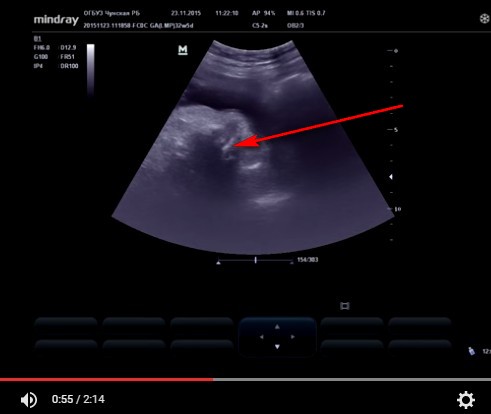

Норма? Или нет..

Носогубный и альвеолярная дуга - точно норма.

Кирилл, там носовая кость ( на что стрелку навели).

Наш случай.

Кадр из лекции Некрасовой Е.С.